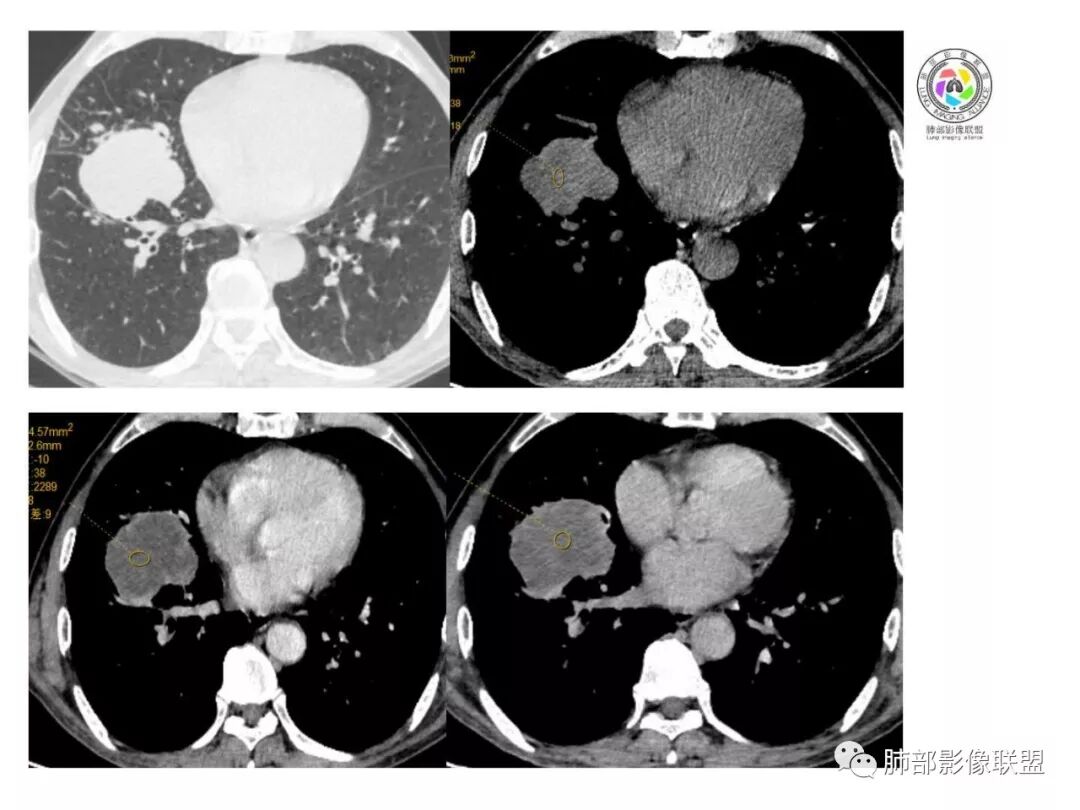

影像表现缺乏特异性,CT最常见的表现是位于周围肺野的实质性肿块,病变部位以上叶多见,常位于胸膜下;

因为病灶有上皮成分和间叶成分,所以兼具肺癌和肺肉瘤的影像学特征,

1.具有肉瘤的特性:肿瘤体积一般较大,直径约大于5cm,边缘清楚、光整,由于肿瘤生长迅速,可见大片坏死,坏死边界清楚;常见支气管推移。

2.具有癌些特性:如分叶、短毛刺、空洞,但是钙化及胸膜凹陷征少见,病灶往往是直接侵犯胸膜,可以远处转移,肺门及纵隔淋巴结可明显肿大;

3.强化方式:增强后病灶以环状强化为主,病灶周边多以癌组织为主,血供丰富,病灶中心区则以肉瘤成分为主,血供较差,易出现粘液样变性、坏死、出血,坏死边界清楚,所以增强CT对PSC与普通型肺癌有一定的鉴别价值。

(中央型PSC肿块常位于肺门处,肿块多较大,边界较光整,伴有阻塞性肺炎或肺不张,与常见类型肺癌不易鉴别。)

1.本病例结合病理结果及影像综合分析,应该符合肉瘤样癌,上皮成分是腺癌为主;肿块的边缘毛刺、分叶及周围癌型淋巴管炎征象有符合腺癌的影像表现之处。

2.肿块巨大局部边缘膨隆、光整,坏死较彻底;明显跨叶生长(途经发育不全叶间裂或肺门,注意患者没有胸水),支气管阻塞伴推移等,这些更符合肉瘤的特性。

3.坏死区边界较清楚(皮囊样),环形强化明显,病灶内血管穿行等,都不符合我们常见的鳞癌。

4.肺肉瘤虽然也是肿块巨大,呈大片状坏死,但是边缘光整圆隆,没有分叶、毛刺征象,较少出现肺门及纵隔淋巴结转移。